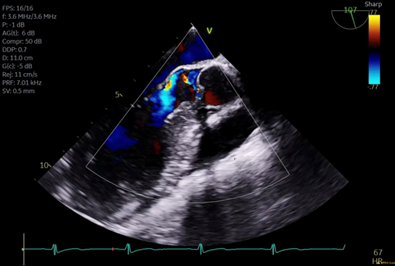

Scenario: 17yo m w/ pmh bicuspid aortic valve with mixed stenosis and regurgitation and dilated aortic root presents for Ross procedure. His pre-operative TEE exam revealed the following

Image 2

1.  What midesophageal TEE views are shown in images 1 and 2?

Image 1 is a mid-esophageal long axis view, typically found at an omniplane angle around 120 degrees. Image 2 is a mid-esophageal aortic valve short axis view, typically found at an omniplane angle between 30 and 60 degrees.

2The mean gradient measured across the aortic valve is 17mmhg. What is the severity of stenosis?

A mean gradient of 17mmhg indicates a mild degree of stenosis. When using gradients to determine severity of aortic stenosis, <20mmhg indicates mild stenosis, 20-40mmhg indicates moderate stenosis, and >40mmhg indicates severe stenosis.